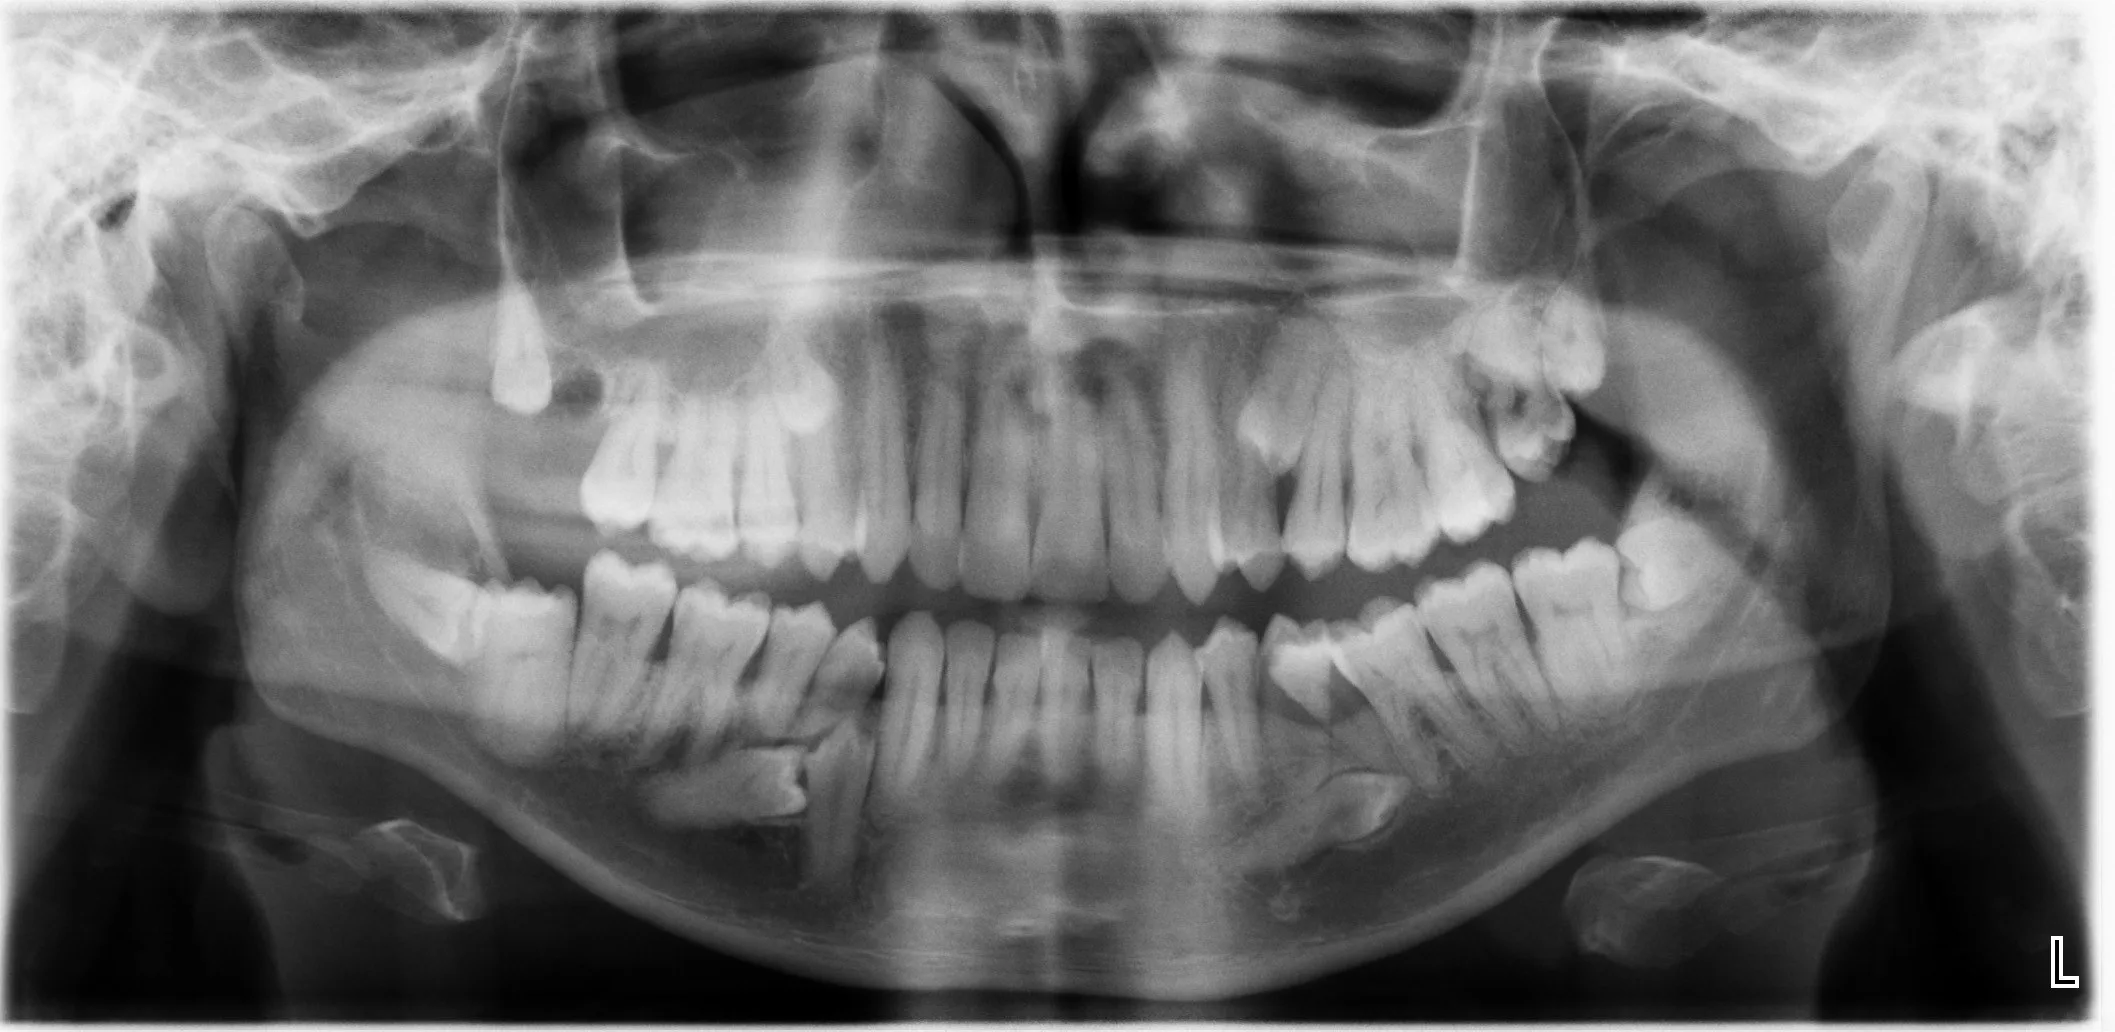

2. Key Image Capture™

• Innovative and proprietary algorithm

• Produces key images from dataset for impacted teeth applications

• Able to be manipulated, annotated and verified by the radiologist

• Report crafted using Report Wizard™

The Report Wizard™ code outputs the key images to further enhance the algorithm accuracy.

60027975173 021 F45 A6 2 D20 4 D53 AF24 FC3956 C4979 F

3. Comprehensive Combined System

Produces annotated key images and written report from a CBCT dataset